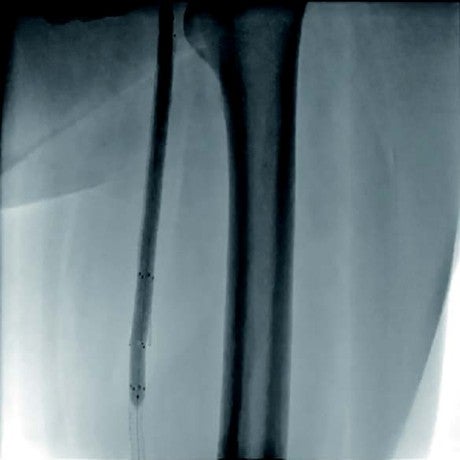

本症例は、初回治療2年後フォローアップ時のエコー所見から、DESの中枢および末梢の病変が閉塞の原因となった可能性が高い。同部位はDCBおよびDESで治療されているにもかかわらず、2年で再狭窄を呈していることから、drug technologyを用いたバルーンおよびステントでの治療は許容できないと判断した。BMI 31.9の肥満であったため右総大腿動脈より対側山越アプローチとした。6 Fr 45 cmガイディングシース + 5.5 Frシースバックアップ下に血管内超音波(IVUS)ガイドで臨んだ。エコー所見どおりDESの中枢および末梢病変は非常に強固であったため、ガイドワイヤー(40 g)で通過した。DES内の病変は非常に柔らかく、ガイドワイヤー(1 g)で通過、DCBのステント内閉塞はガイドワイヤー(15 g)を用い、IVUS下に確実に真腔内で通過した。0.014 inchガイドワイヤーの場合、ガイドワイヤーはステントストラットを容易に通過する。そのため、複数方向からの透視やIVUSを用いることで、確実にステント内を通過していることを確認することが必要となる。また、ステント内はhealthy landingではないことから、確実に前回のステントを最低1 cm以上越えて留置すべきである。DESの再狭窄は、culprit以外が柔らかい赤色血栓であることが多く、この症例もガイドワイヤーの感覚から同様の所見が疑われた。末梢塞栓予防に造影カテーテルによる可及的血栓吸引を行い、バルーン4.0 mm × 300 mmで前拡張をした。末梢病変はバイアバーン® ステントグラフト6 mm × 150 mmを留置、中枢は左浅大腿動脈起始部から10 mmのhealthy landingが残存していたため、同部位よりステントグラフト6 mm × 150 mmを留置した(図1)。高耐圧バルーン6.0 mm × 150 mmで後拡張を行い(図2、図3)、十分にgainを確保し良好なflowで終了した。治療時間は40分、造影剤使用量は70 mL であった。